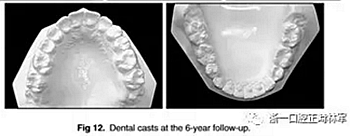

6年后治療結(jié)果保持穩(wěn)定(圖11,圖12 ; 圖13)??梢杂^察到穩(wěn)定的間隙關(guān)閉,正常的覆蓋和覆合,上下牙中線一致,微笑美觀。建議完美替代了拔除的側(cè)切牙。正畸治療后進行牙齒美白。